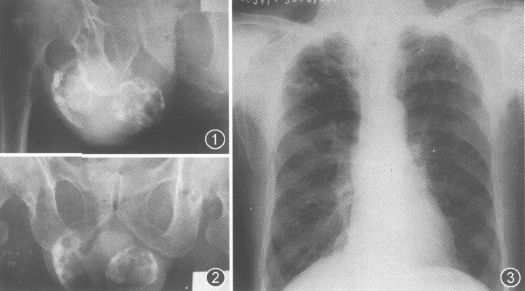

照片名称:附睾及睾丸结核钙化

照片名称:正常胸片